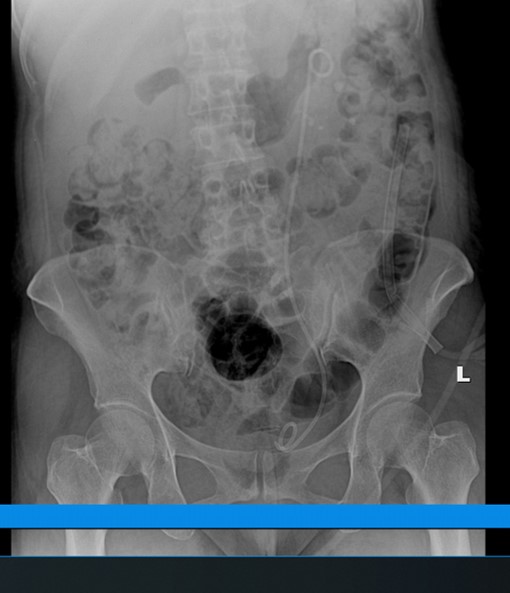

Bệnh nhân nữ, 56 tuổi xuất hiện đau âm ỉ vùng thắt lưng trái nhiều ngày, đau tăng dần, không thành cơn, không lan, không có liên quan bữa ăn, không có tư thế giảm đau, tiểu buốt, bệnh nhân được gia đình đưa đến khám tại Bệnh viện đa khoa quốc tế Hải Phòng. Sau khi thăm khám, thực hiện cận lâm sàng, bác sĩ phát hiện người bệnh có sỏi san hô thận trái kích thước lớn 5,6cm gây giãn đài bể thận trái.

Xác định tình trạng của bệnh nhân nếu không được điều trị sẽ gây ra những biến chứng như: Viêm thận, ứ nước thận và đặc biệt là suy thận, các bác sĩ Khoa Ngoại thận tiết niệu và Nam học quyết định thực hiện tán sỏi qua da đường hầm nhỏ. Kíp thực hiện đã tiến hành rạch da khoảng 0,5cm vùng thắt lưng, tạo một đường hầm nhỏ từ ngoài da vào thận, đưa máy nội soi qua đường hầm tìm sỏi. Sau đó quan sát thấy 1 viên sỏi bể thận trái rất cứng và lớn, kích thước 5×6 cm, hình xù xì như san hô ở bể thận và đài thận. Nhanh chóng sử dụng tia Laser tán vỡ sỏi thành từng mảnh nhỏ và hút các mảnh sỏi vỡ ra ngoài qua đường hầm. Kiểm tra phim chụp sau mổ đánh giá, người bệnh đã sạch sỏi so với phim cũ, sức khỏe ổn định, tinh thần thoải mái và đã được xuất viện.